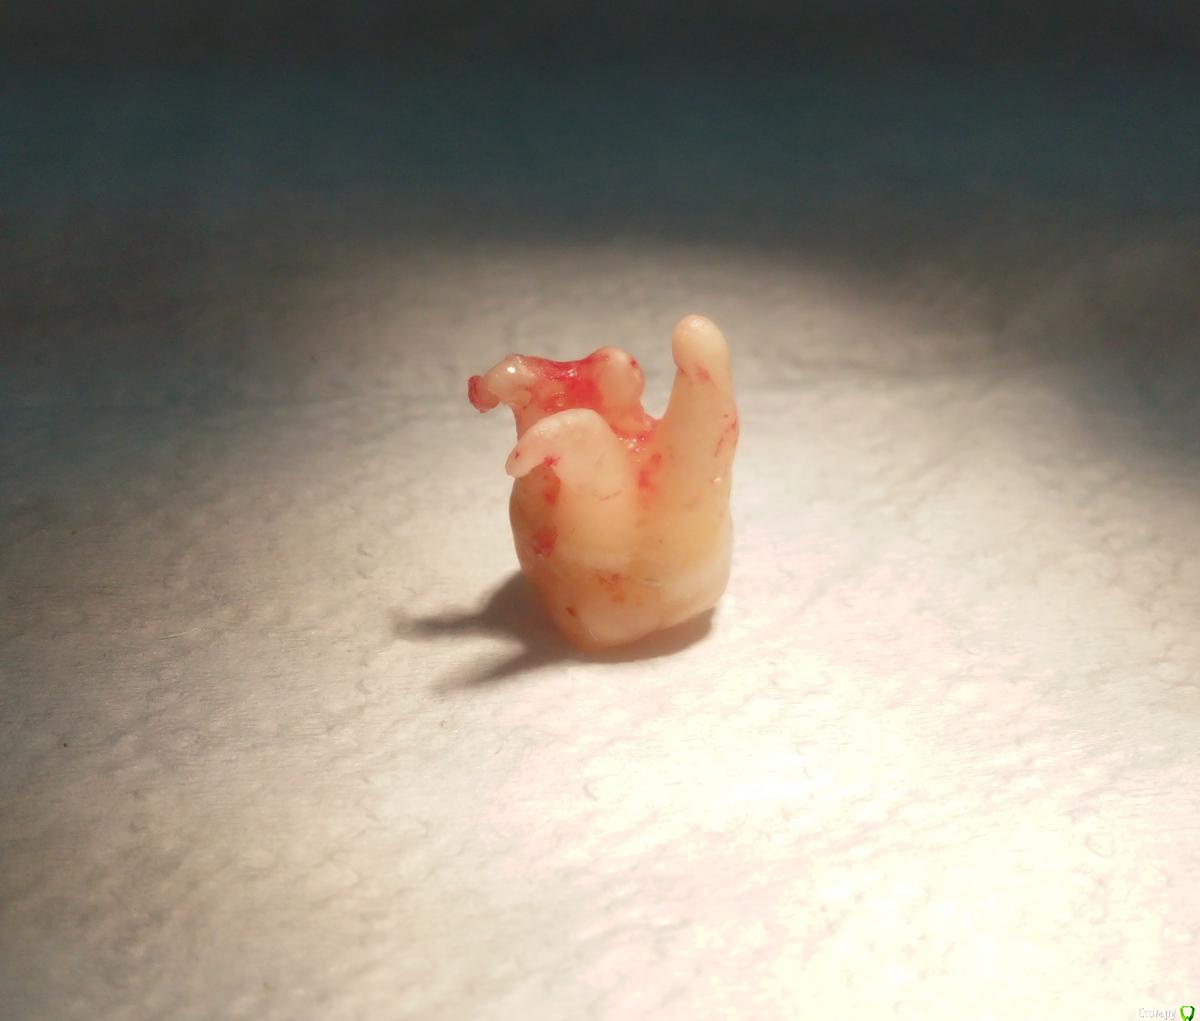

Фарид Расулыч Опубликовано 8 мая, 2015 Поделиться Опубликовано 8 мая, 2015 Засранец на выходе сделал "хрусть" ))http://s006.radikal.ru/i214/1505/bf/6b3a753040b4.jpg 6 Ссылка на комментарий

chervoncevdaniil Опубликовано 8 мая, 2015 Поделиться Опубликовано 8 мая, 2015 Засранец на выходе сделал "хрусть" ))http://s006.radikal.ru/i214/1505/bf/6b3a753040b4.jpgЧем доставали апекс? Ссылка на комментарий

Фарид Расулыч Опубликовано 8 мая, 2015 Поделиться Опубликовано 8 мая, 2015 (изменено) терапевтической гладилкой.На удаление основной части зуба ушло 5 минут. Корешок + 15 минут Изменено 8 мая, 2015 пользователем Фарид Расулыч Ссылка на комментарий

chervoncevdaniil Опубликовано 8 мая, 2015 Поделиться Опубликовано 8 мая, 2015 Прямым элеватором со стороны 7 вывихивали?Кость пилили где нибудь? Ссылка на комментарий

Фарид Расулыч Опубликовано 8 мая, 2015 Поделиться Опубликовано 8 мая, 2015 В основном прямым. Кость только чуть чуть. Чтоб гладилкой зацепиться Ссылка на комментарий